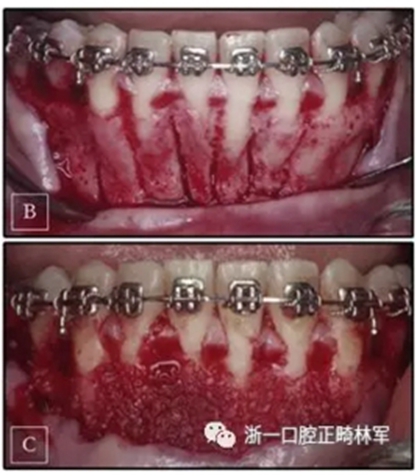

正畸矯治器放置后,將牙弓矯平并對齊。一旦這一階段完成,將下頜切牙區(qū)的唇側(cè)部分,即從左側(cè)尖牙到右側(cè)尖牙,進行翻瓣,并放置凍干的骨移植物(圖4)。 手術(shù)后一周,制作一個長方形不銹鋼的開口環(huán),并在第一磨牙近中形成止點,并放置以進行深覆蓋的矯正。每7至10天對患者進行評估以在完全骨再礦化之前激活矯正裝置。 在5個月內(nèi)完全糾正深覆蓋,并將臨時支抗裝置放置在下頜右側(cè)尖牙的遠中,以使右側(cè)頰部部分向前移動。 為了幫助這種前移,使用短的II類牽引。

圖4. A,手術(shù)計劃; B,選擇性壓力側(cè)翻瓣過程; C,植入材料。